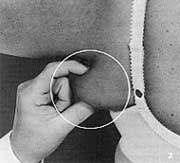

- The circle focuses on a pad of fat sometimes called “double breast.”

- The pinch test gives an indication of the amount of fat buildup.

1-2. The physician indicates the type of fat that can be helped by liposuction.